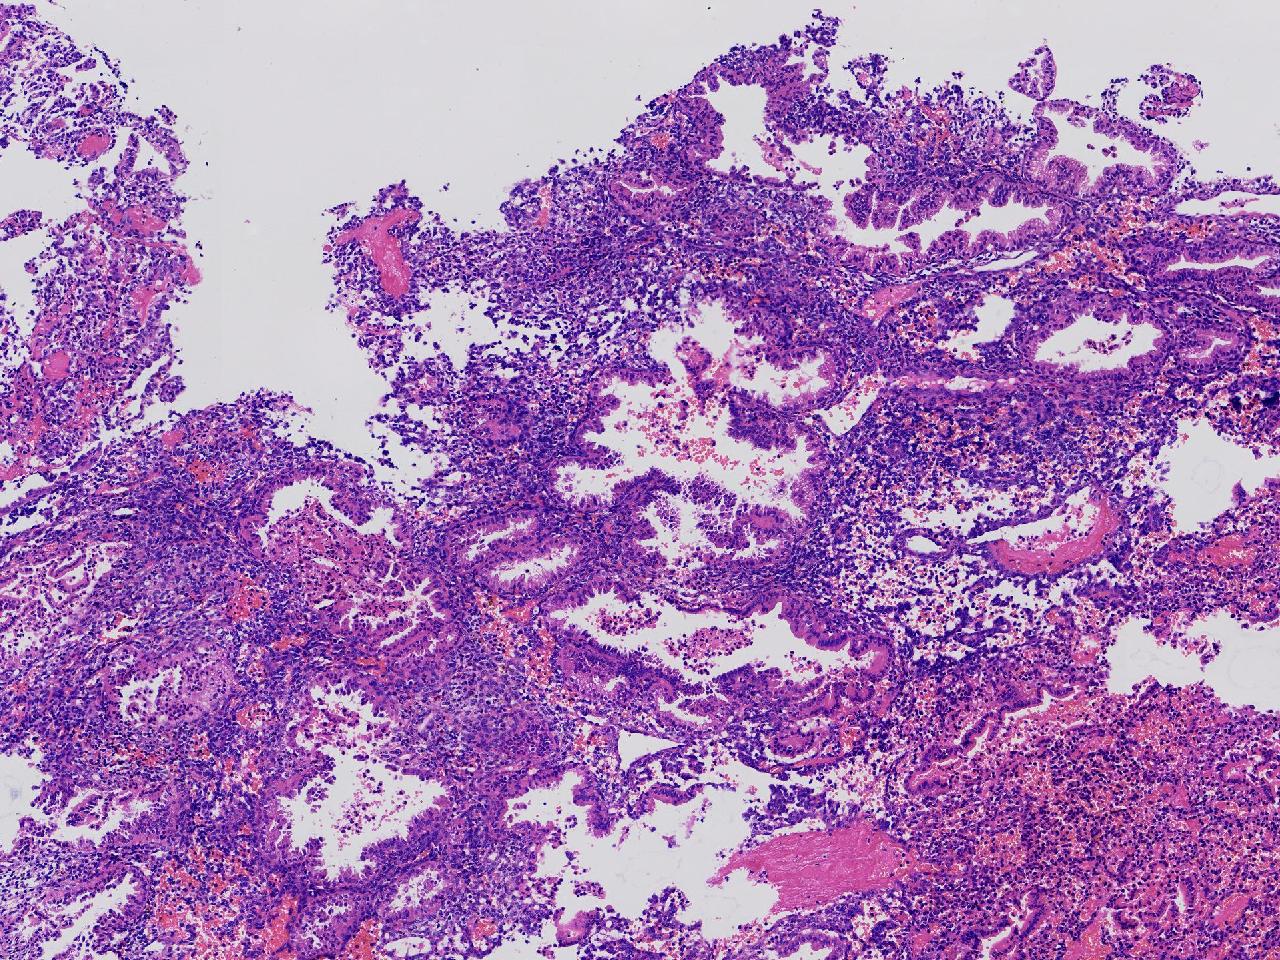

性别

女

年龄

45岁

临床诊断

阴道不规则出血20余天,

一般病史

彩超示:宫腔内见约41X11毫米的不均质回声区。宫腔镜示:宫腔形态正常,内膜粉红,不规则增厚。

标本名称

子宫内膜

大体所见

灰粉色不整形软组织多块,1.5X1X0.6厘米。

分泌反应子宫内膜,伴有出血。

晚泌期及月经早期改变,局部呈啫酸性乳头状化生改变。